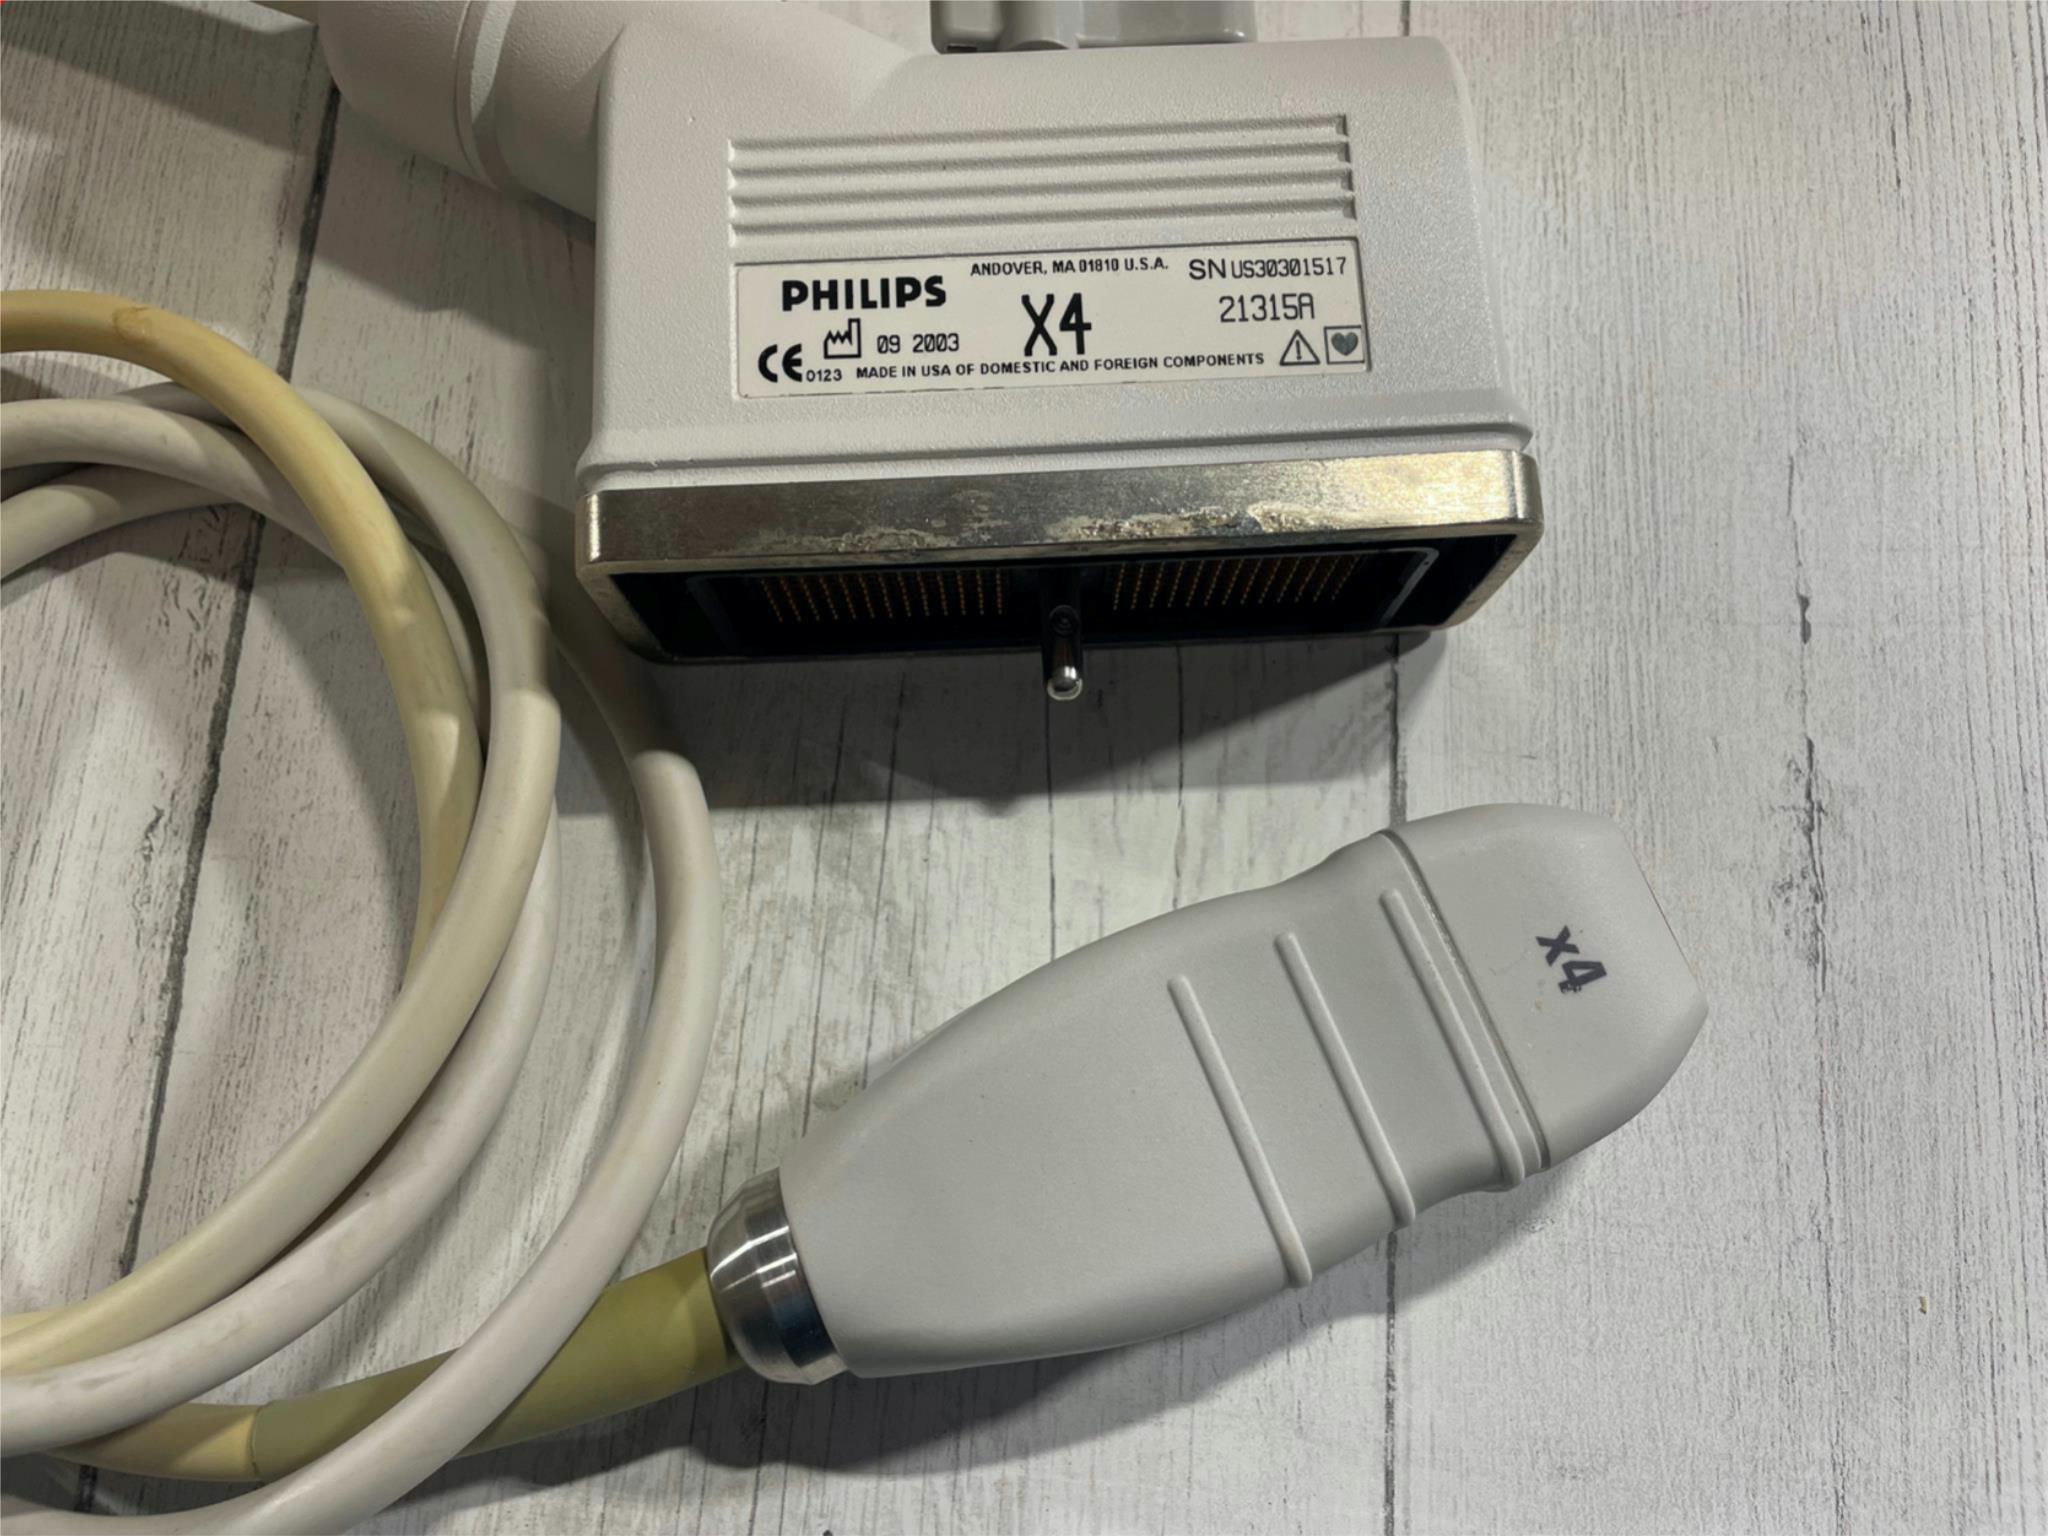

Philips x4 Ultrasound Probe Transducer 2003

Sale price$ 1,638.36

DIAGNOSTIC ULTRASOUND MACHINES FOR SALE

Philips x4 Ultrasound Probe Transducer 2004

Sale price$ 1,310.68